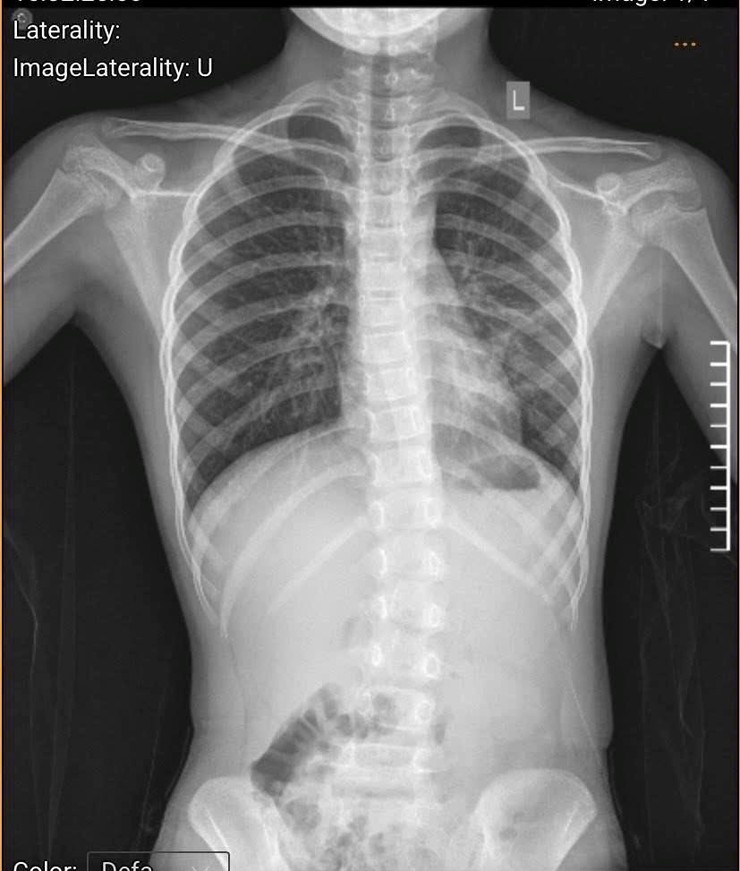

Bệnh nhi là cháu Trịnh Minh H. (9 tuổi, trú tại phường Sơn Tây, Hà Nội), đến khám tại bệnh viện với biểu hiện ho kéo dài nhiều ngày không khỏi. Qua thăm khám, các bác sĩ chẩn đoán trẻ bị viêm phế quản. Tuy nhiên, trong quá trình đánh giá toàn diện, bác sĩ nhận thấy trẻ có dấu hiệu bất thường về tư thế và hình thể như đau mỏi lưng kéo dài, dáng đi lệch.

Nghi ngờ bệnh lý cột sống, bệnh nhi được chỉ định chụp X-quang, dựng hình cột sống và đo chỉ số Cobb. Kết quả xác định trẻ bị cong vẹo cột sống còn khả năng điều trị bằng phương pháp phục hồi chức năng, chưa cần can thiệp ngoại khoa.

Bệnh viện đa khoa Sơn Tây khuyến cáo cần sớm phát hiện cong vẹo cột sống ở trẻ nhỏ- Ảnh 1.

Ngay sau đó, khoa Nhi đã hội chẩn liên khoa với khoa Phục hồi chức năng để xây dựng phác đồ điều trị phù hợp. Bệnh nhi được hướng dẫn tập vận động cột sống thắt lưng có trợ giúp, thời gian 20 phút mỗi ngày. Sau khi xuất viện, trẻ tiếp tục duy trì các bài tập trị liệu tại nhà theo hướng dẫn của bác sĩ nhằm cải thiện tình trạng cong vẹo.